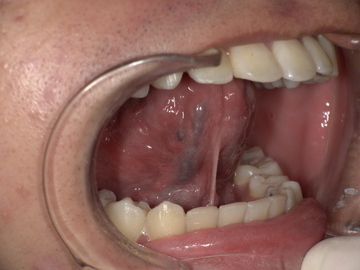

After

舌小帯形成術後、舌の動きがスムーズになり、上あごにしっかりと届くようになりました。これにより、発音に必要な舌の動きが改善されます。